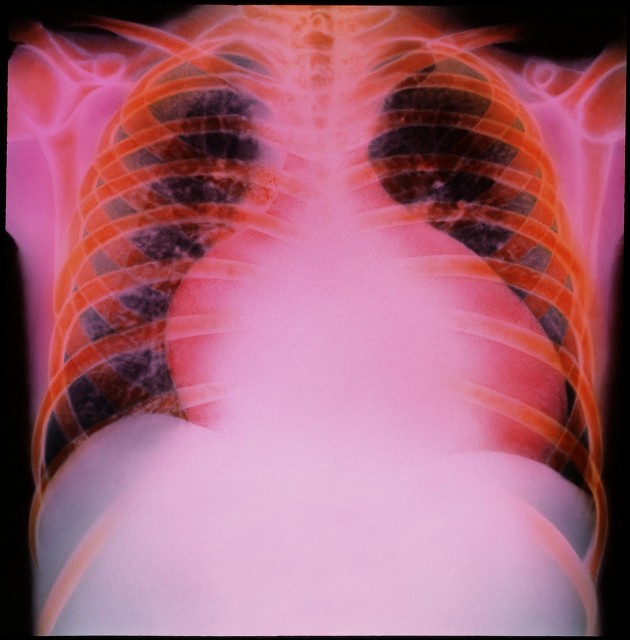

林某槽,男性,74岁,一个反复咳喘十余年的老肺病病人,长期咳嗽,气喘,一到冬天就发作,一喘就是一个月,没完没了,走路都困难,上不了楼梯,走不了一百步,平常血压又低。在家需要辅助吸氧治疗,自备吸氧机,每天吸氧二三次,一次大概吸半小时到一小时,生活质量挺差的。 医院诊断:“慢性阻塞性肺病急性发作,慢性肺源性心脏病,冠状动脉粥样硬化性心脏病,心绞痛,心功能3级。”

这次因为感冒再次诱发咳嗽,气喘,呼吸困难,不能平卧,下肢水肿来住院。经过检查诊断:“慢性阻塞性肺病急性加重,慢慢肺源性心脏病,冠状动脉粥样硬化性心脏病,心力衰竭”。